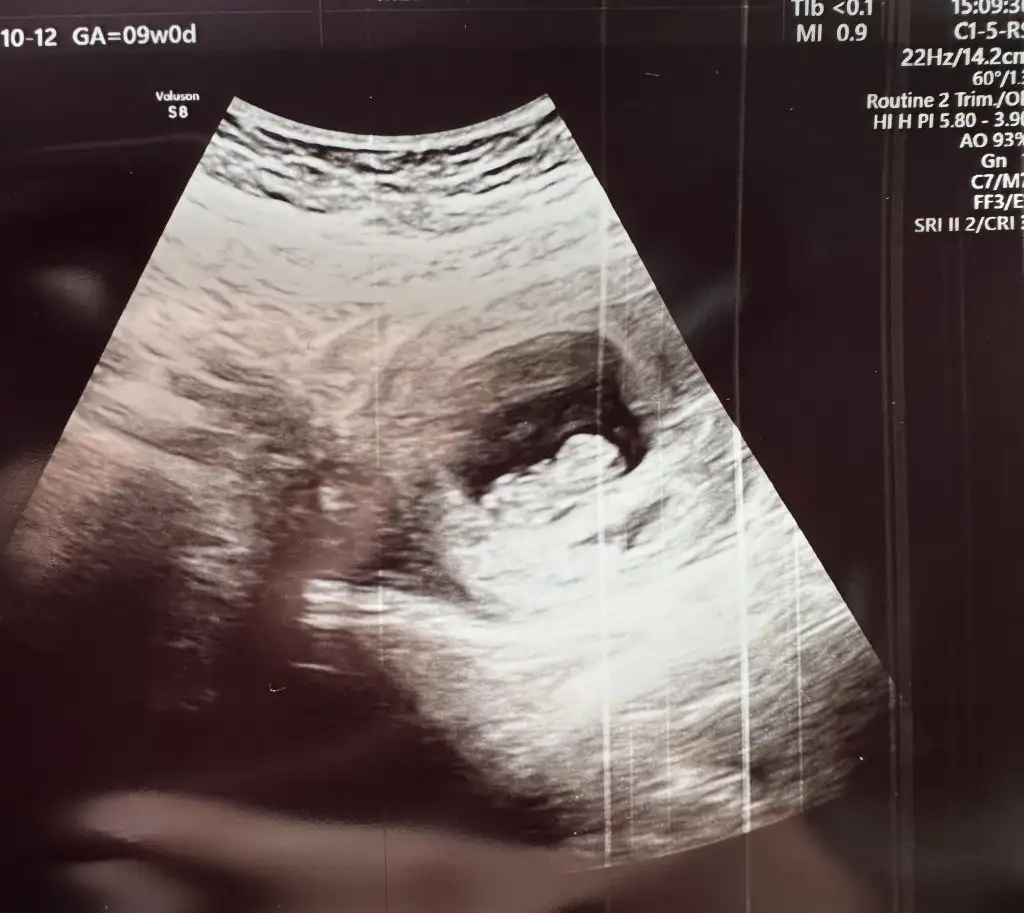

1ciftyesilgozz hayirli olsun merak ediyordum cinsiyeti hayirli olsun. benim iki oglumda sagdaydi agrisinda çürücek diyordum artik sende tutmuş. simdiki solda insallah sizin tahminler tutar bizdede